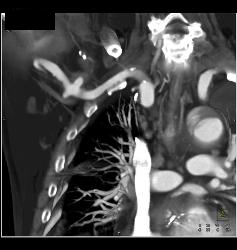

Pulmonary Embolism (PE) in Left Lobe Lung